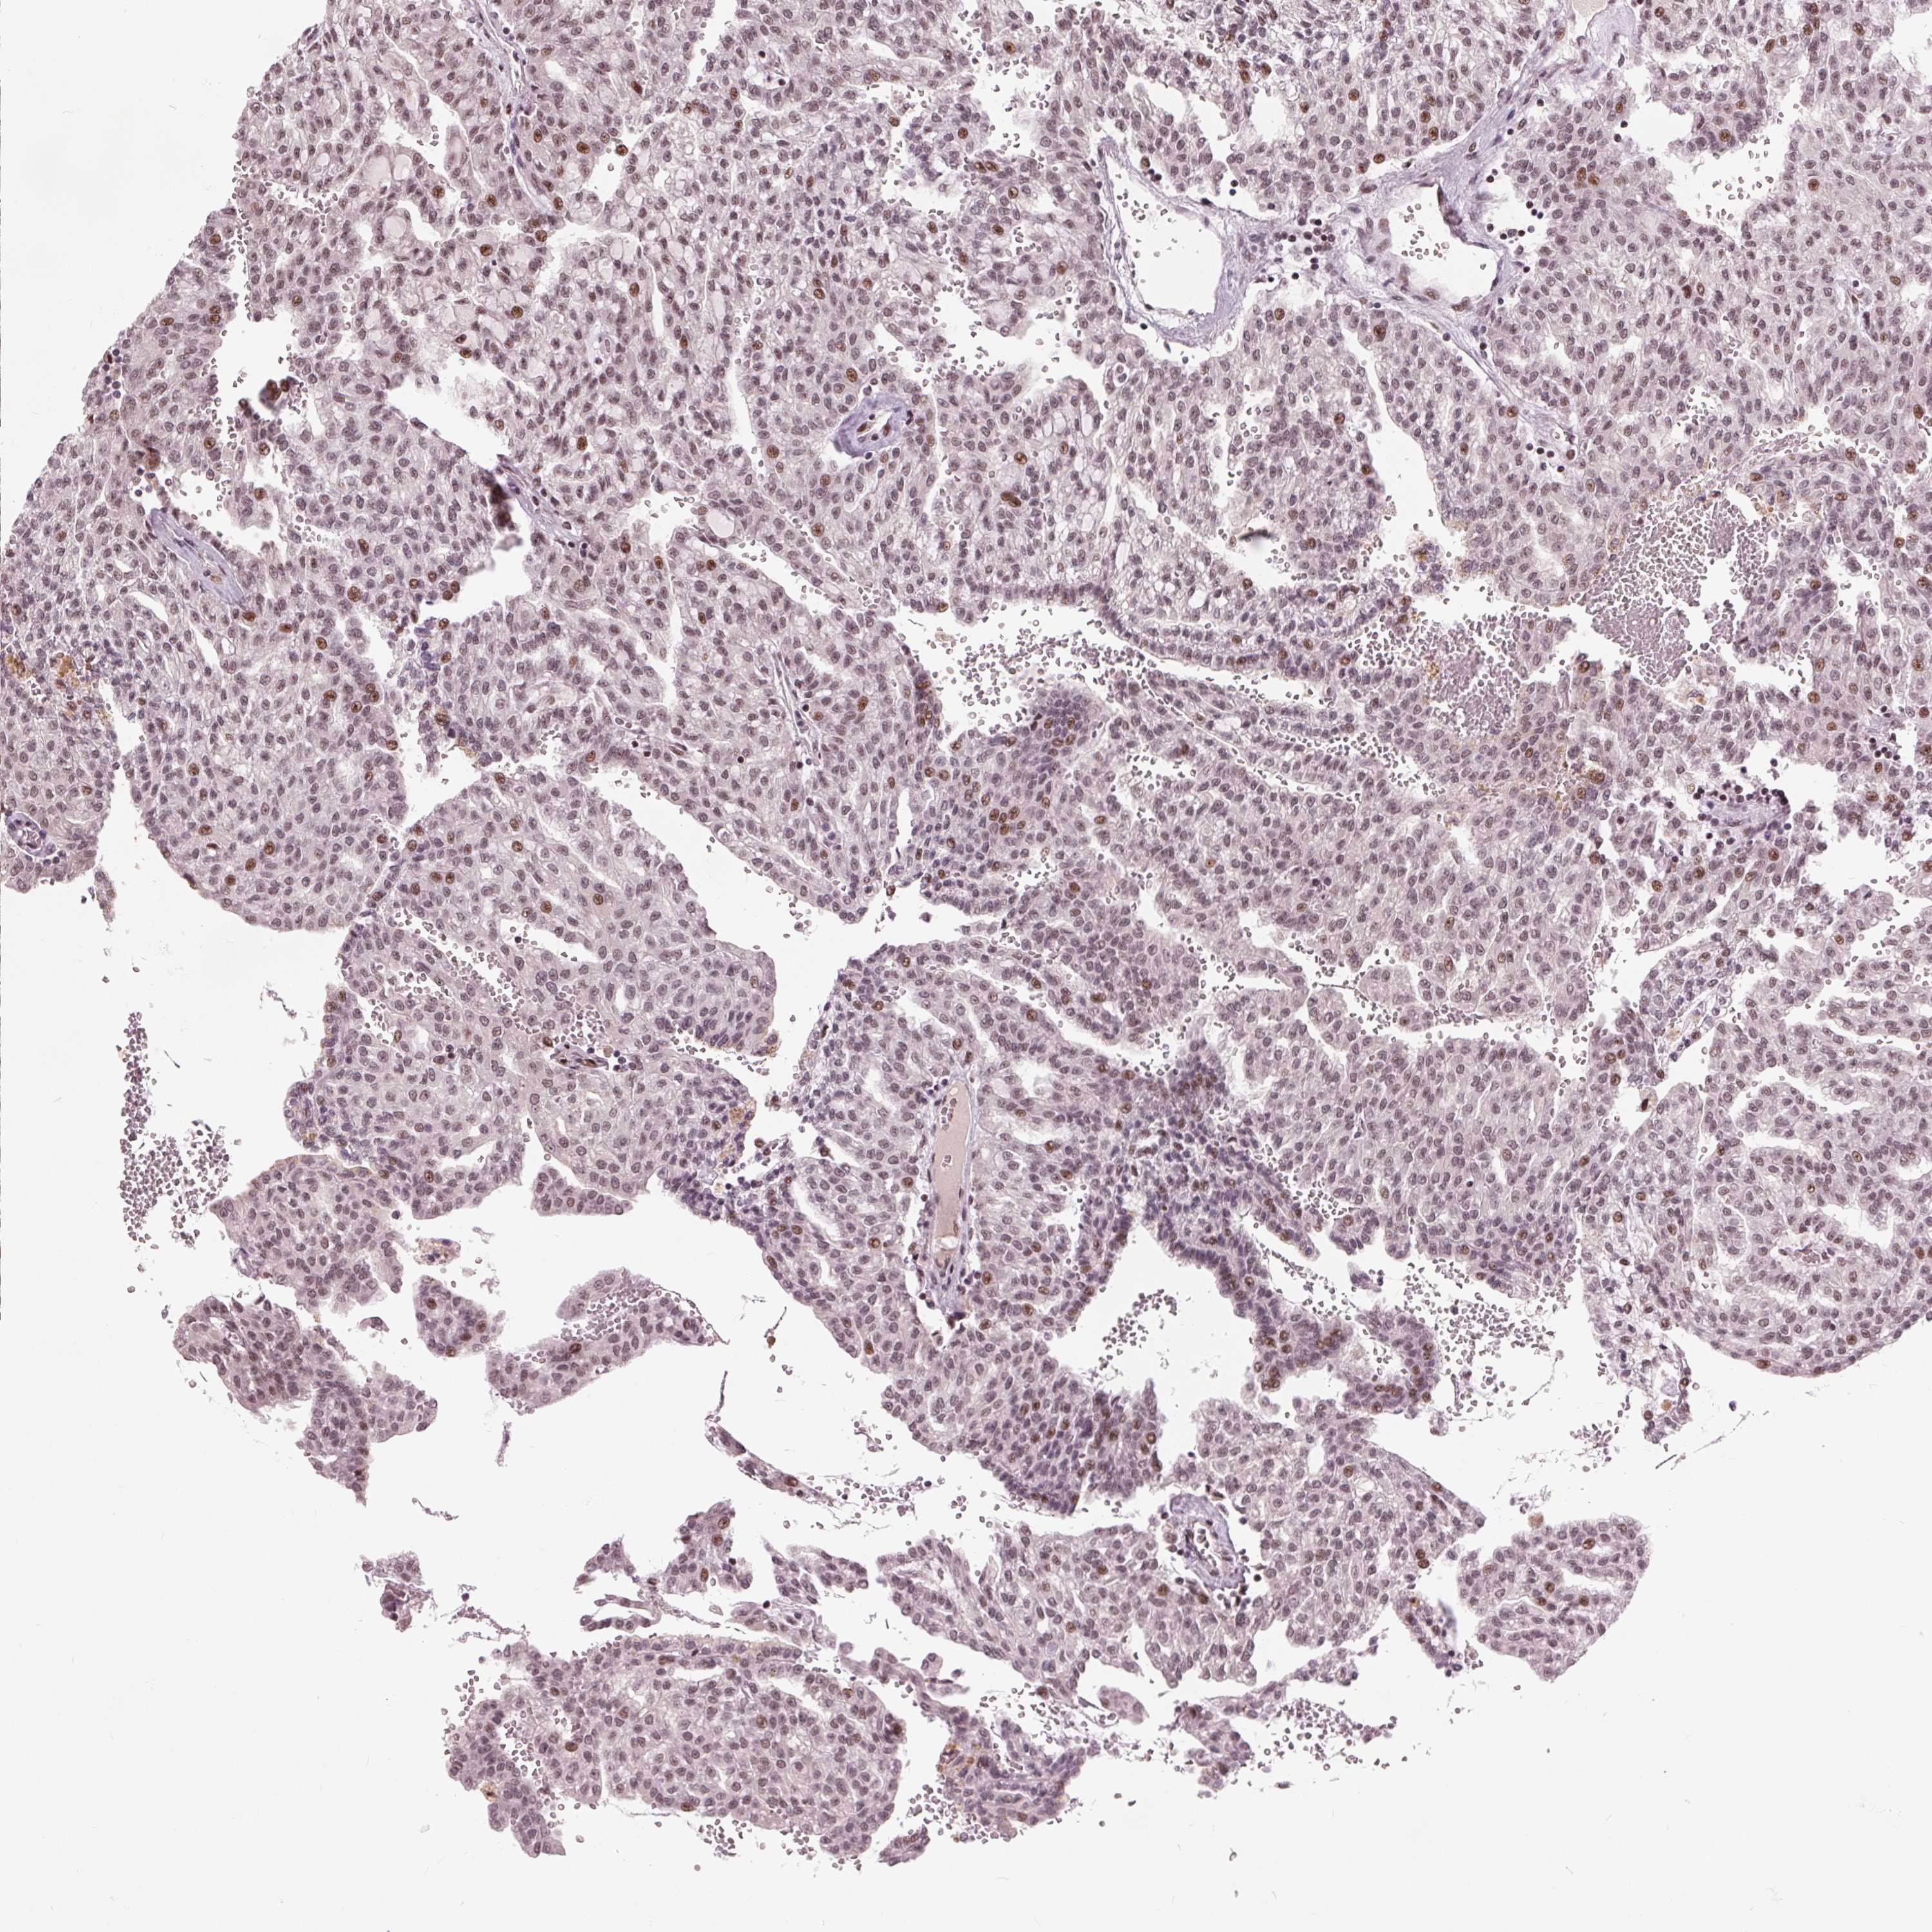

KIDNEY RENAL CLEAR CELL CARCINOMA (VALIDATION) - Interactive survival scatter ploti

The Survival Scatter plot shows the clinical status (i.e. dead or alive) for all individuals in the patient cohort, based on the same data that underlies the corresponding Kaplan-Meier plots. Patients that are alive at last time for follow-up are shown in blue and patients who have died during the study are shown in red.

The x-axis shows the expression levels (FPKM) of the investigated gene in the tumor tissue at the time of diagnosis. The y-axis shows the follow-up time after diagnosis (years). Both axes are complimented with kernel density curves demonstrating the data density over the axes. The top density plot shows the expression levels (FPKM) distribution among dead (red) and alive patients (blue). The right density plot shows the data density of the survived years of dead patients with high and low expression levels respectively, stratified using the cutoff indicated by the vertical dashed line through the Survival Scatter plot. This cutoff is automatically defined based on the FPKM cutoff that minimizes the p-score. The cutoff can be changed by dragging the vertical line or by entering a cutoff value in the square labeled "Current cut-off".

Under the Survival Scatter plot the p-score landscape (black curve; left axis) is shown together with dead median separation (red curve; right axis). Dead median separation is the difference in median mRNA expression between patients who have died with high and low expression, respectively. It is calculated as follows: median FPKM expression of dead patients with high expression - median FPKM expression of dead patients with low expression. This is intended to aid the user in visually exploring custom cutoffs and the associated p-scores and dead median separation.

Individual patient data is displayed and can be filtered by clicking on one or more of the category buttons on the top of the page. Categories describing expression level and patient information include: high, low, alive, dead, female, male and tumor stages. The scale of the x-axis can be toggled between linear and log-scale by clicking on the "x log" button. Mouse-over function shows TCGA ID, patient information and mRNA expression (FPKM) for each patient.

& Survival analysisi

Kaplan-Meier plots summarize results from analysis of correlation between mRNA expression level and patient survival. Patients were divided based on level of expression into one of the two groups "low" (under cut off) or "high" (over cut off). X-axis shows time for survival (years) and y-axis shows the probability of survival, where 1.0 corresponds to 100 percent.

TTC34 is not prognostic in Kidney Renal Clear Cell Carcinoma (validation)

TCGA RNA samplesi

RNA-seq data is reported as average FPKM (number Fragments Per Kilobase of exon per Million reads), generated by the The Cancer Genome Atlas (TCGA) .

Normal distribution across the dataset is visualized with box plots, shown as median and 25th and 75th percentiles. Points are displayed as outliers if they are above or below 1.5 times the interquartile range. FPKM values of the individual samples are presented next to the box plot.

Average pTPM 0.3

Number of samples 100